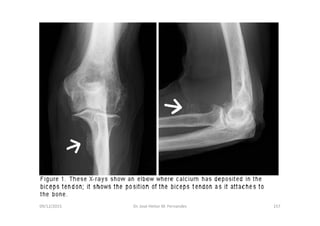

09/12/2015 Dr. José Heitor M. Fernandes 157

LUXAÇÃO DO COTOVELO E FRATURA DA CABEÇA DO RÁDIO:

Fig. 1 – Luxação posterior do cotovelo isolada.

Fig. 2 – Luxação posterior do cotovelo associada à fratura da cabeça do rádio.

Fig. 3 – Luxação lateral do cotovelo isolada.